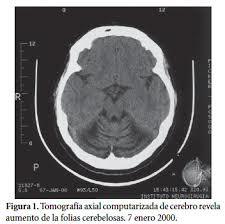

1. Agenesia

1. hipoplasia

1. Arnold Chiari

1. lesiones vasculares

1. Alteraciones metabolicas

1. Atrofias cerebelosas

1. Traumatismos